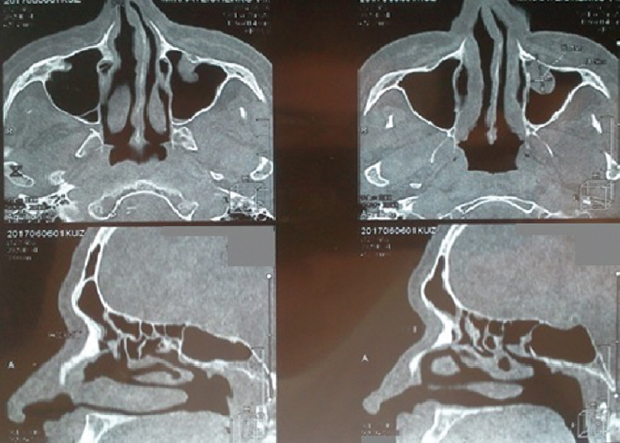

На рентгенограмме придаточных пазух носа (ППН) с 2007 по 2016 г. — утолщение слизистой оболочки гайморовых пазух с признаками осумкованной жидкости справа. На МСКТ ППН в марте 2017 г. выявлен левосторонний пансинусит (рис. 2).

Рис. 2. Мультиспиральная компьютерная томография придаточных пазух носа. Выявлен левосторонний пансинусит. Пристеночное утолщение слизистой оболочки правой половины лобной пазухи, правой верхнечелюстной и основной пазухи. Носовой цикл нарушен. Искривление носовой перегородки